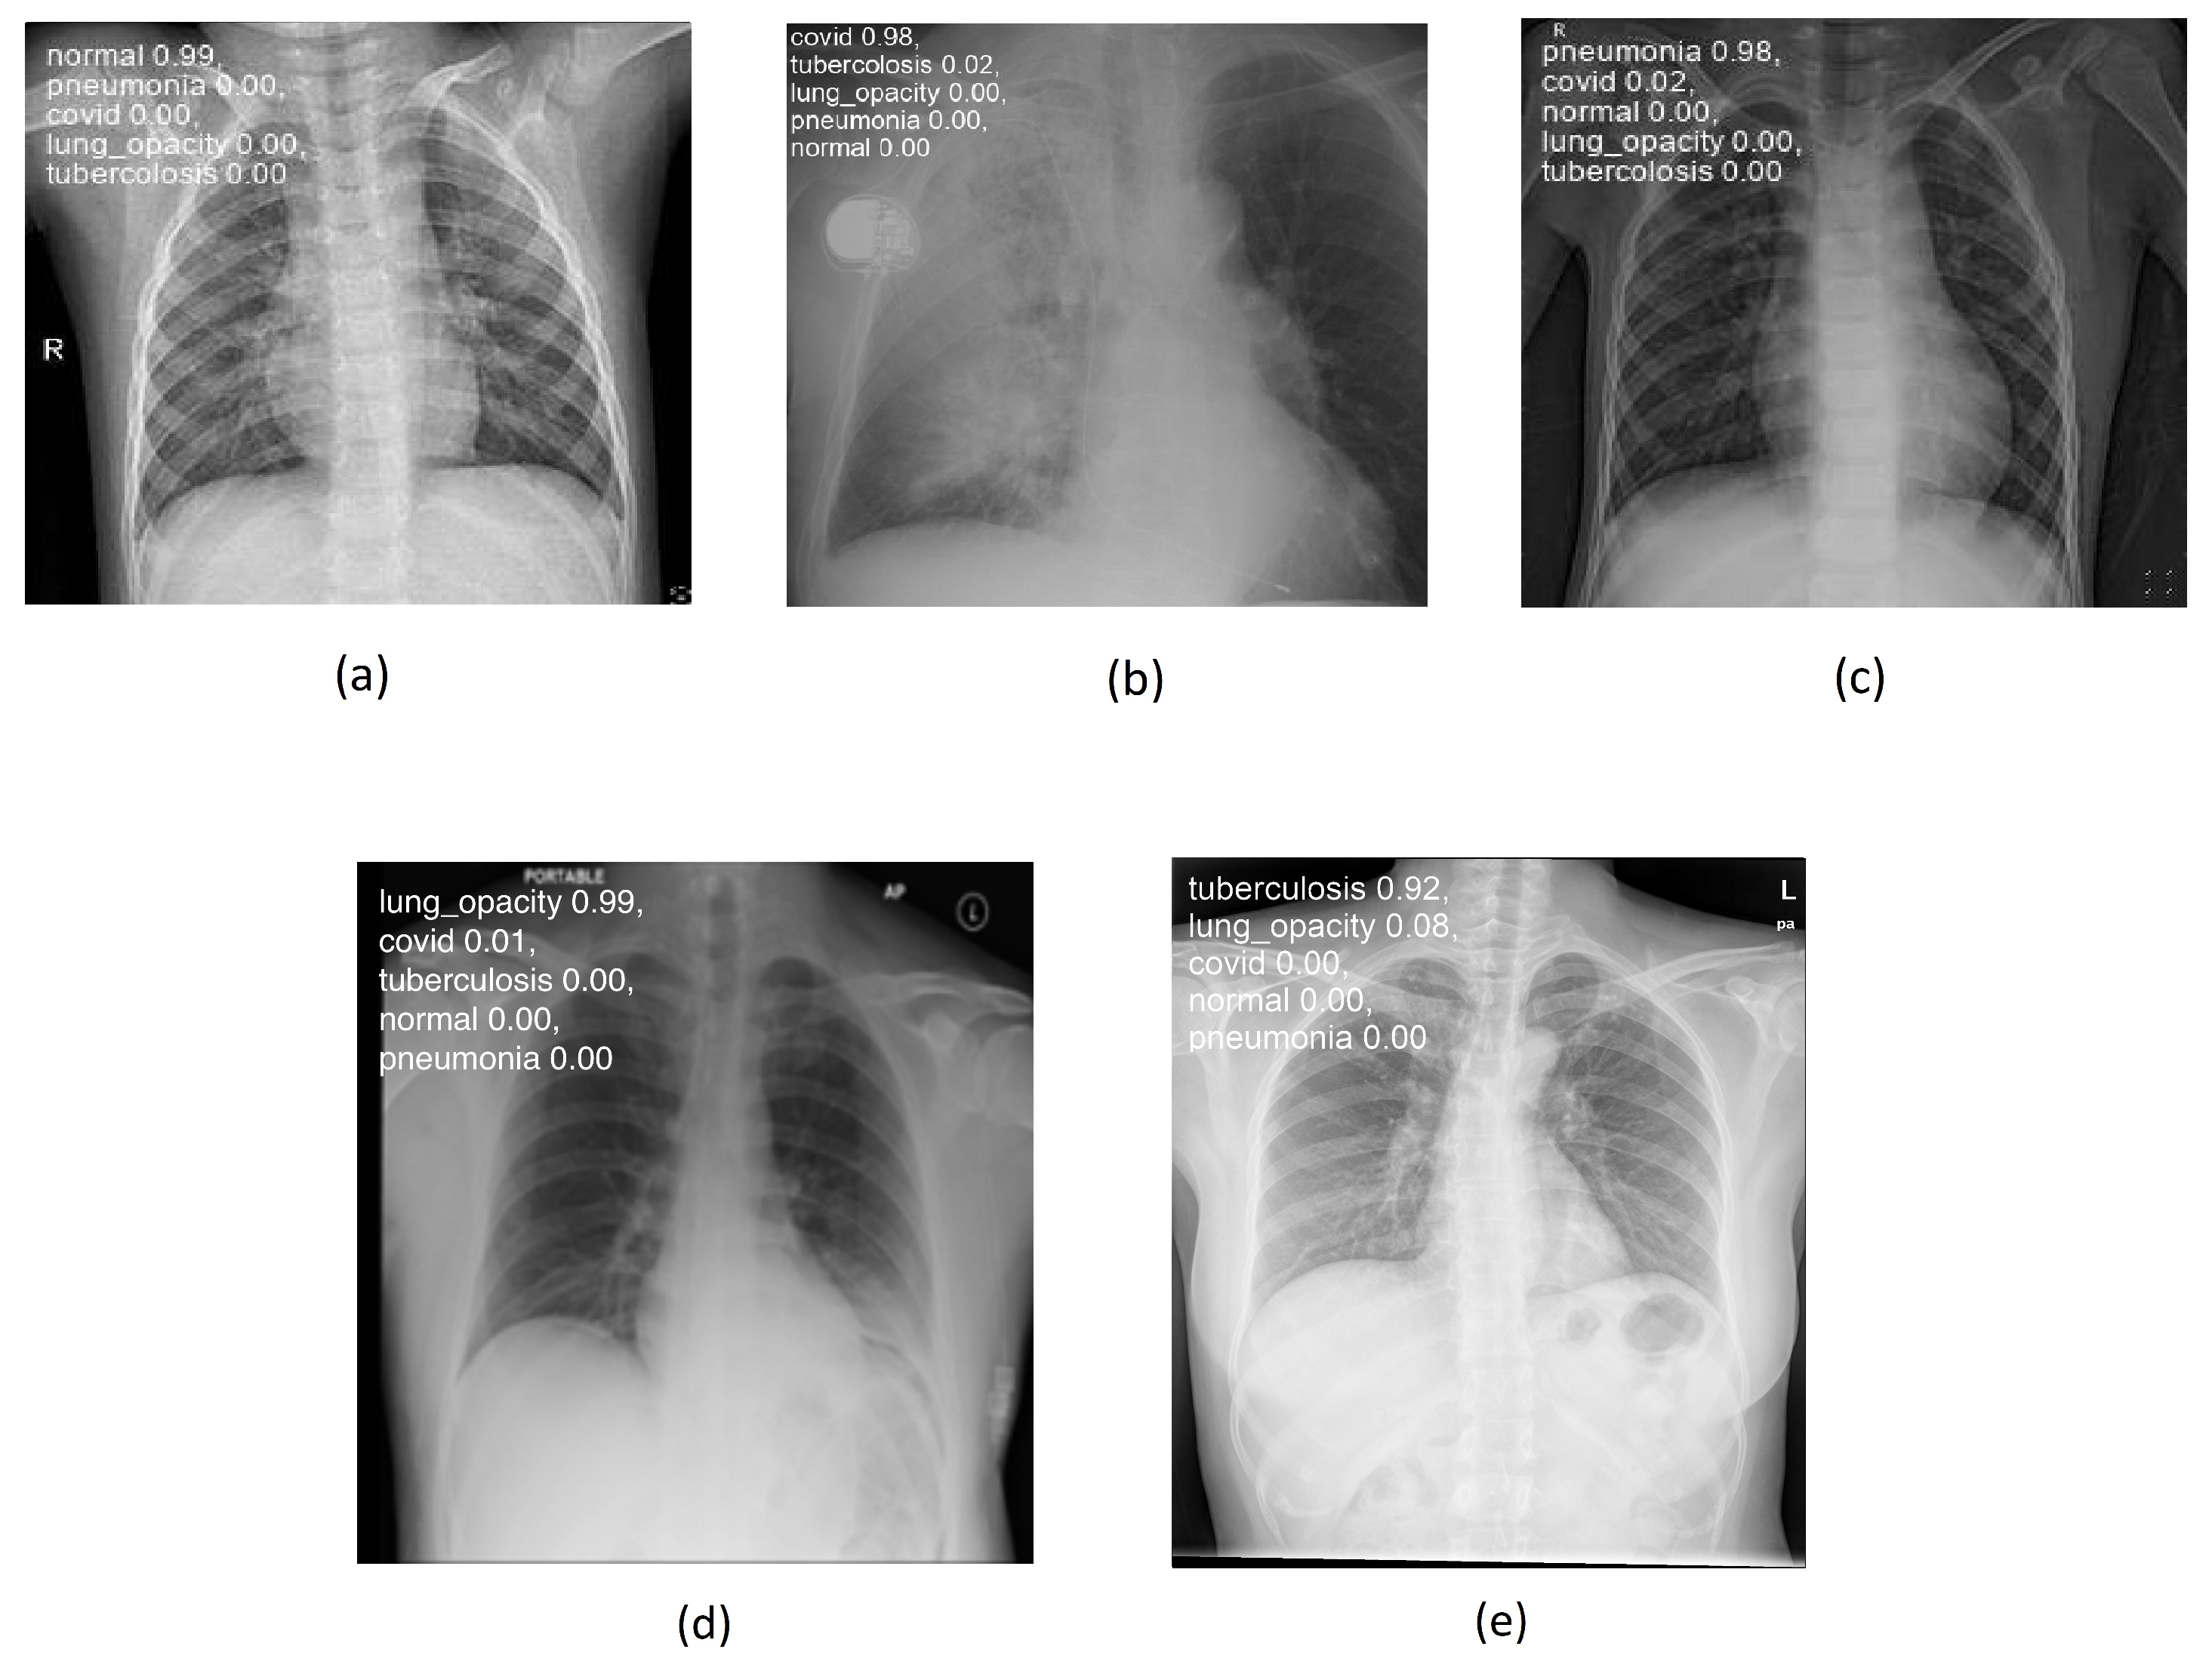

Figure 4a–e below illustrate the “normal”, “covid”, “lung_opacity”, “pneumonia”, and “tuberculosis” classes.

Figure 8 shows some examples of lung images, each corresponding to its respective pathology, with the classification percentage result for all classes. As can be observed, the model performs very well even on images it has never seen before, achieving a rate of accuracy ranging from 92 to 99%.

Figure 4. Chest images for (a) “normal”, (b) “covid”, (c) “pneumonia”, (d) “lung_opacity”, and (e) “tuberculosis” classes.

Figure 8. Lung disease classification for (a) “normal”, (b) “covid”, (c) “pneumonia”, (d) “lung_opacity”, and (e) “tuberculosis” classes using testing set.